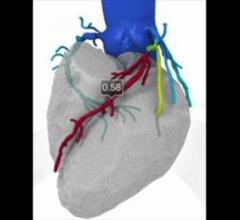

June 29, 2016 — HeartFlow Inc. announced that it is launching its next generation of the HeartFlow FFR-CT Analysis. The ...

Here is a recap of some of the top trends and new technology at the Society of Cardiovascular Computed Tomography (SCCT) ...

DAIC Editor Dave Fornell shares some of the most innovative new technologies shown on the expo floor and discusses in ...